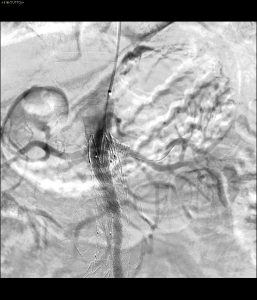

- Ricanalizzazione renale

- Controllo finale con ottimo risultato angiografico

- È stata eseguita una cateterizzazione selettiva attraverso il “free flow” della protesi.

- È stato posizionato con successo uno stent Express LD (6×18 mm, Boston Scientific), ripristinando immediatamente la perfusione dell’organo.

Il risultato finale dell’intervento è stato ottimale:

- Pervietà completa di entrambe le arterie renali.

- Flusso sanguigno eccellente attraverso lo stent Viabahn.